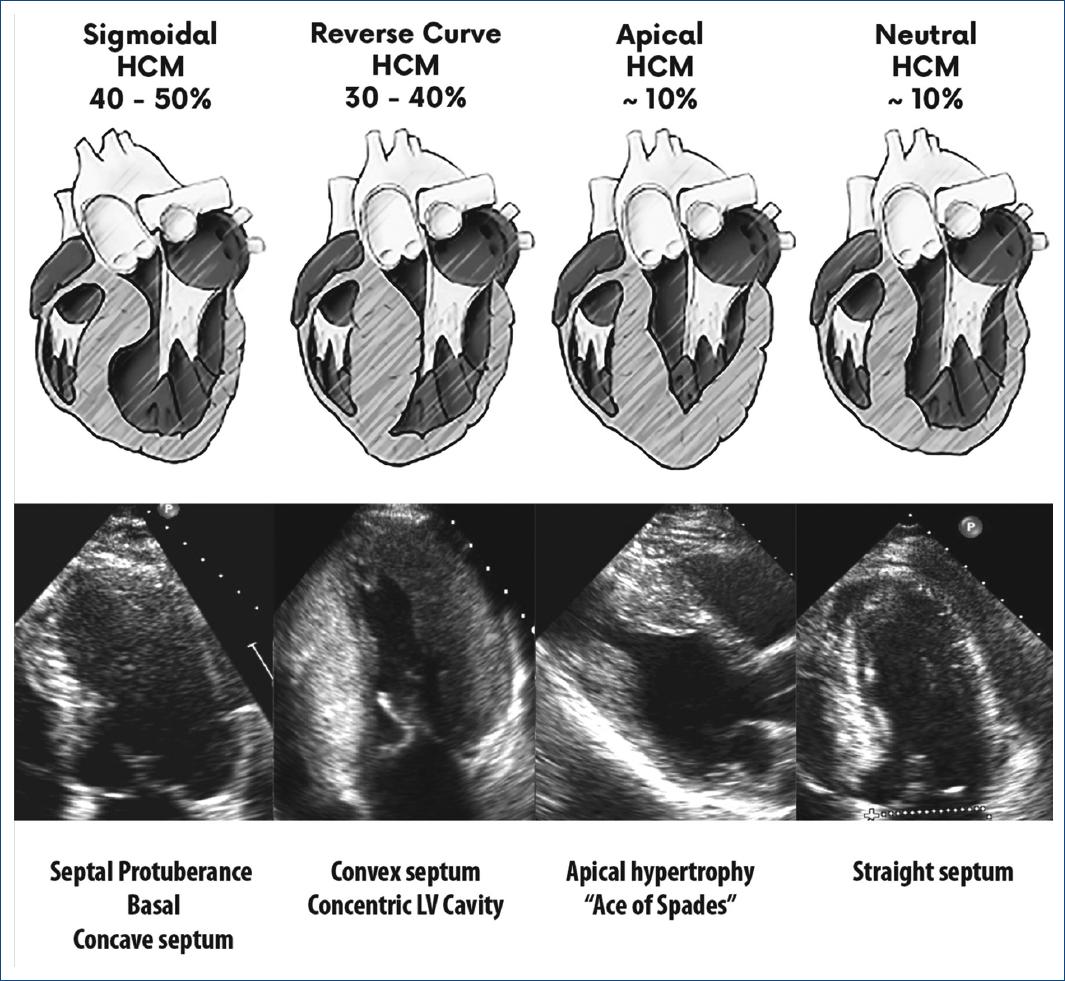

Since then, more than an anatomical classification, the concept of phenotype has been used to refer to the morphological and functional aspects of HCM. The most common morphologies of the septum and the distribution of hypertrophy in the left ventricular wall in patients with HCM (phenotypic expression) are shown in figure 5. In fact, this distribution has been used to subdivide the condition into these more commonly identified 4 groups.

Figure 5 The most common morphologies of the HCM, showing the frequency of presentation and their anatomical characteristics. SIGMOID: prominent basal septal protuberance, concave septum and ovoid left ventricular cavity; REVERSE CURVATURE: convex septum, increasing left ventricular cavity; APICAL: hypertrophy of the apical portion ± middle segments, “Ace of spades” shaped cavity (More frequent in Asia); NEUTRAL: uniform hypertrophic septum.

As it has already been mentioned, although there are four phenotypic types which are considered as the most frequent in terms of the location of hypertrophy, such as basal sigmoid hypertrophy (with LVOT obstruction), reverse curvature hypertrophy (which usually corresponds to mid-ventricular hypertrophy, and may have mid-ventricular obstruction and/or AA), apical and neutral hypertrophy; in general, some of them may coexist in the same patient, or even have atypical or mixed localization components. A greater extent of left ventricular hypertrophy has been associated with a younger age and a mitral valve with a higher degree of SAM of the valve and outflow obstruction, but it has not been shown to be related to the magnitude of the symptoms or to the gender.